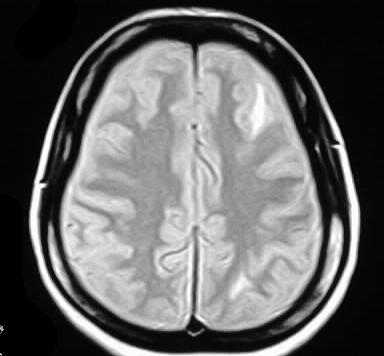

МРТ головного мозга при системной красной волчанке

Системная красная волчанка (СКВ) относится к аутоимммунным васкулитам, около 7% пациентов имеют поражение головного мозга. Патологические изменения проявляются в виде периваскулярного воспаления и пролиферации эндотелиальных клеток. 90% СКВ наблюдается у женщин и начинается с детского возраста. Заболевание затрагивает праактически все органы и системы. Диагноз ставится на основании клинических проявлений и лабораторных исследований (антитела в крови). Критерии сформулированы Американским Колледжем Ревматологов.

При МРТ головного мозга выявляются очаги, гиперинтенсивные на Т2-взвешенных МРТ, диффузная атрофия, венозные тромбозы, инсульты и кровоизлияния. МРТ головного мозга типа ДВИ показывает изменения только у 10-15% пациентов. Надо отметить, что МР-ангиография, как правило,не показывает изменений в крупных сосудах. Очень редко отмечаются стенозы в ветвях сосудов Виллизиева круга, приводящие даже к территориальным инфарктам. Однако МР-венография нередко показывает тромбоз пораженного синуса, как проявление антифосфодипидного синдрома.

При МРТ в СПб мы проводим дифференциальную диагностику, в первую очередь, с рассеянным склерозом. В отличие от демиелинизаций при СКВ на МРТ головного мозга нет характерного расположения очагов, напротив, имеются корковые очаги и ОНМК. При МРТ головного мозга наиболее затруднительна дифференциальная диагностика с лакунарными инфарктами, которые также могут быть проявлением поражения пенетрирующих сосудов при СКВ.

МРТ головного мозга. Т2-взвешенная аксиальная МРТ. Корково-подкорковые очаги при системной красной волчанке.

Очаги при МРТ головного мозга одинаково хорошо визуализируются в высоких полях и открытых МРТ.